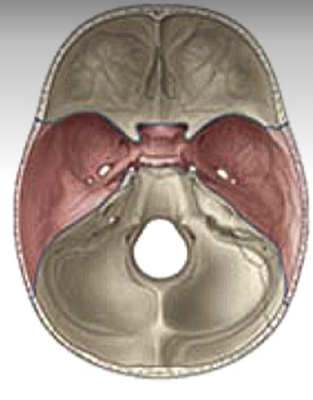

What bones form the anterior cranial fossa?

Frontal, ethmoid and sphenoid

What bones form the middle cranial fossa

Sphenoid and temporal bones

What forms the posterior cranial fossa?

Occipital, temporal, parietal and sphenoid bones

What is this?

Anterior cranial fossa

Middle cranial fossa